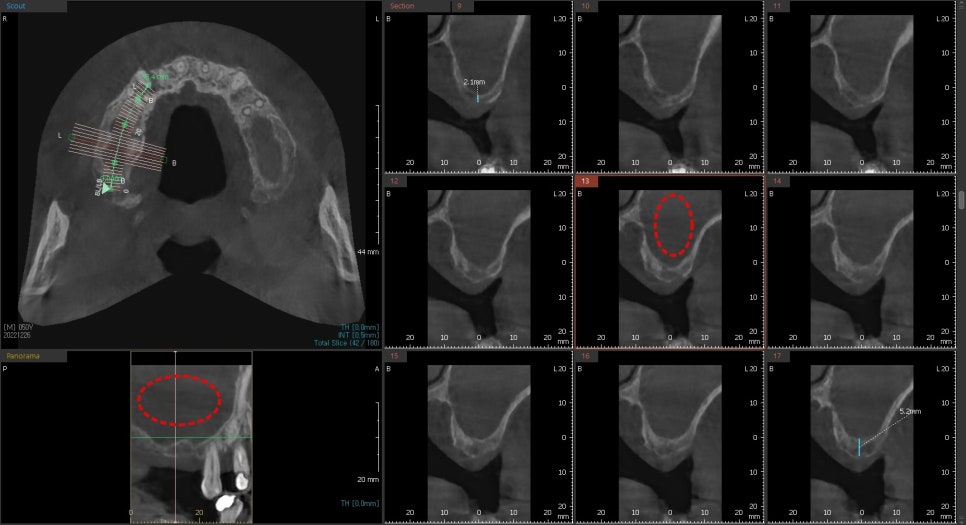

진단을 하기 전에 상악동 공간에 뿌옇게

염증소견이 보였습니다.

CT상에서 회색으로 보이는 공간은

만성비염에 의해 점막의 비후는 물론이고

염증이 차 있는 것을 볼 수 있습니다.

저 해당 공간은 상악동거상술을 통한

치조골 이식술을 해야 하는 공간입니다.

현재 상태에서는 적절하게 점막을 거상할 수 없기 때문에

이비인후과와 협진을 통해 비염수술을 완료 한 후에

위턱뼈의 임플란트 수술을 진행하기로 했습니다.